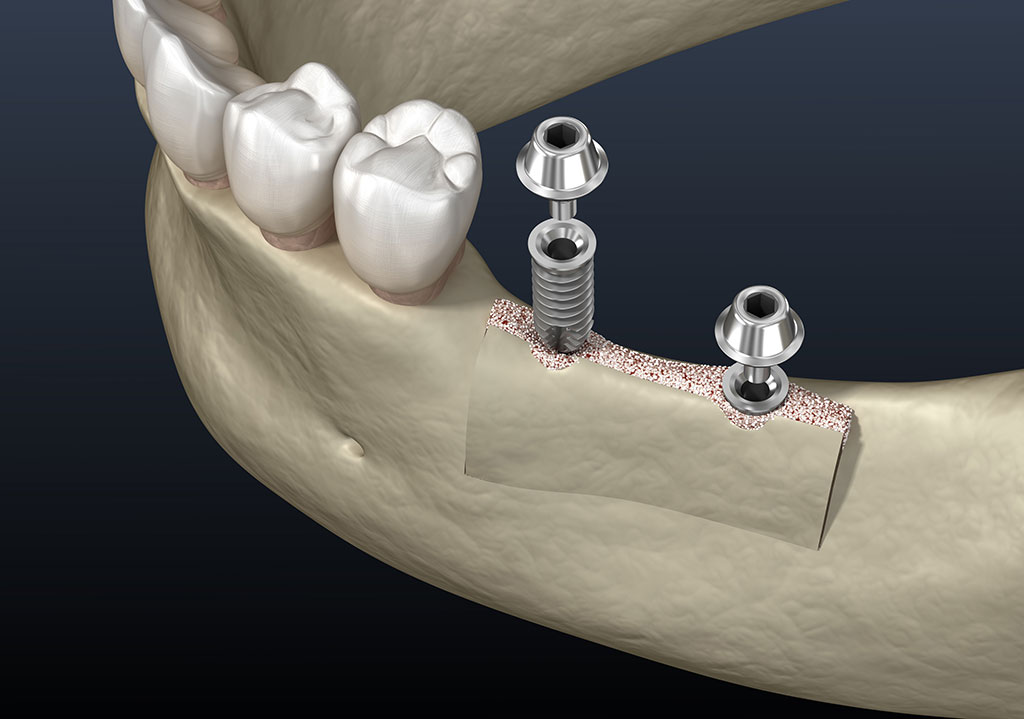

A csontpótlás (bone grafting) egy olyan sebészeti eljárás, amelynek célja a hiányzó vagy sérült csontszövet pótlása, regenerálása. Ezt az eljárást gyakran alkalmazzuk fogászati és szájsebészeti beavatkozások során, különösen, ha a páciensnek nincs elegendő csontja például egy fogimplantátum beültetéséhez. A csontpótlás nemcsak a csont mennyiségét növeli, hanem serkenti a szervezet saját csontképző folyamatát is, így az újonnan létrejött csont természetes módon integrálódik a környező szövetekkel.

A csonthiány, csontveszteség legfőbb okai: foghúzások, különböző gyulladások, fertőzések, traumák, parodontózis, tumorok.

Számos módszer és anyag áll rendelkezésre a csontpótláshoz, így a megfelelő eljárás kiválasztása a páciens egyéni szükségleteitől és a szakorvos döntésétől függ. A beavatkozás célja mindig a páciens hosszú távú egészségének biztosítása és a fogászati funkciók helyreállítása. A csontosódási időszak (oszteointegráció) 6-10 hónap.

Autograft (páciens saját csont). A csontpótláshoz szükséges szövetet a páciens saját szájüregéből nyerjük, az állcsont más részeiből.

Xenograft (állati eredetű csont). Leggyakrabban sertésből és szarvasmarhából származó csontot használunk, amelyet speciálisan előkészítenek és tisztítanak, hogy biztonságosan beültethető legyen az emberi szervezetbe. Előnye, hogy nagy mennyiségben elérhető és nem igényel kiegészítő műtétet, viszont lassabb lehet az integráció az emberi csontszövethez képest.